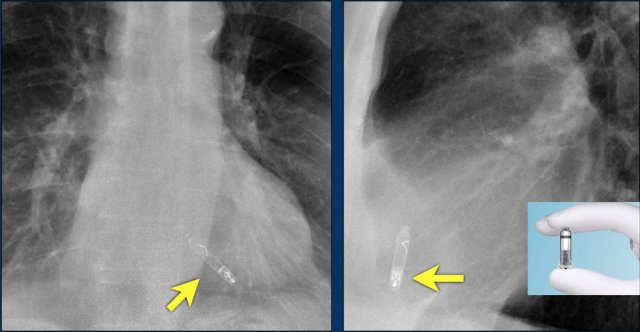

Wiireless pacemaker device

A Micra device is a small wireless pacemaker device, that is transfemorally implanted in the apex of the right ventricle.

Close up view of the Micra device.